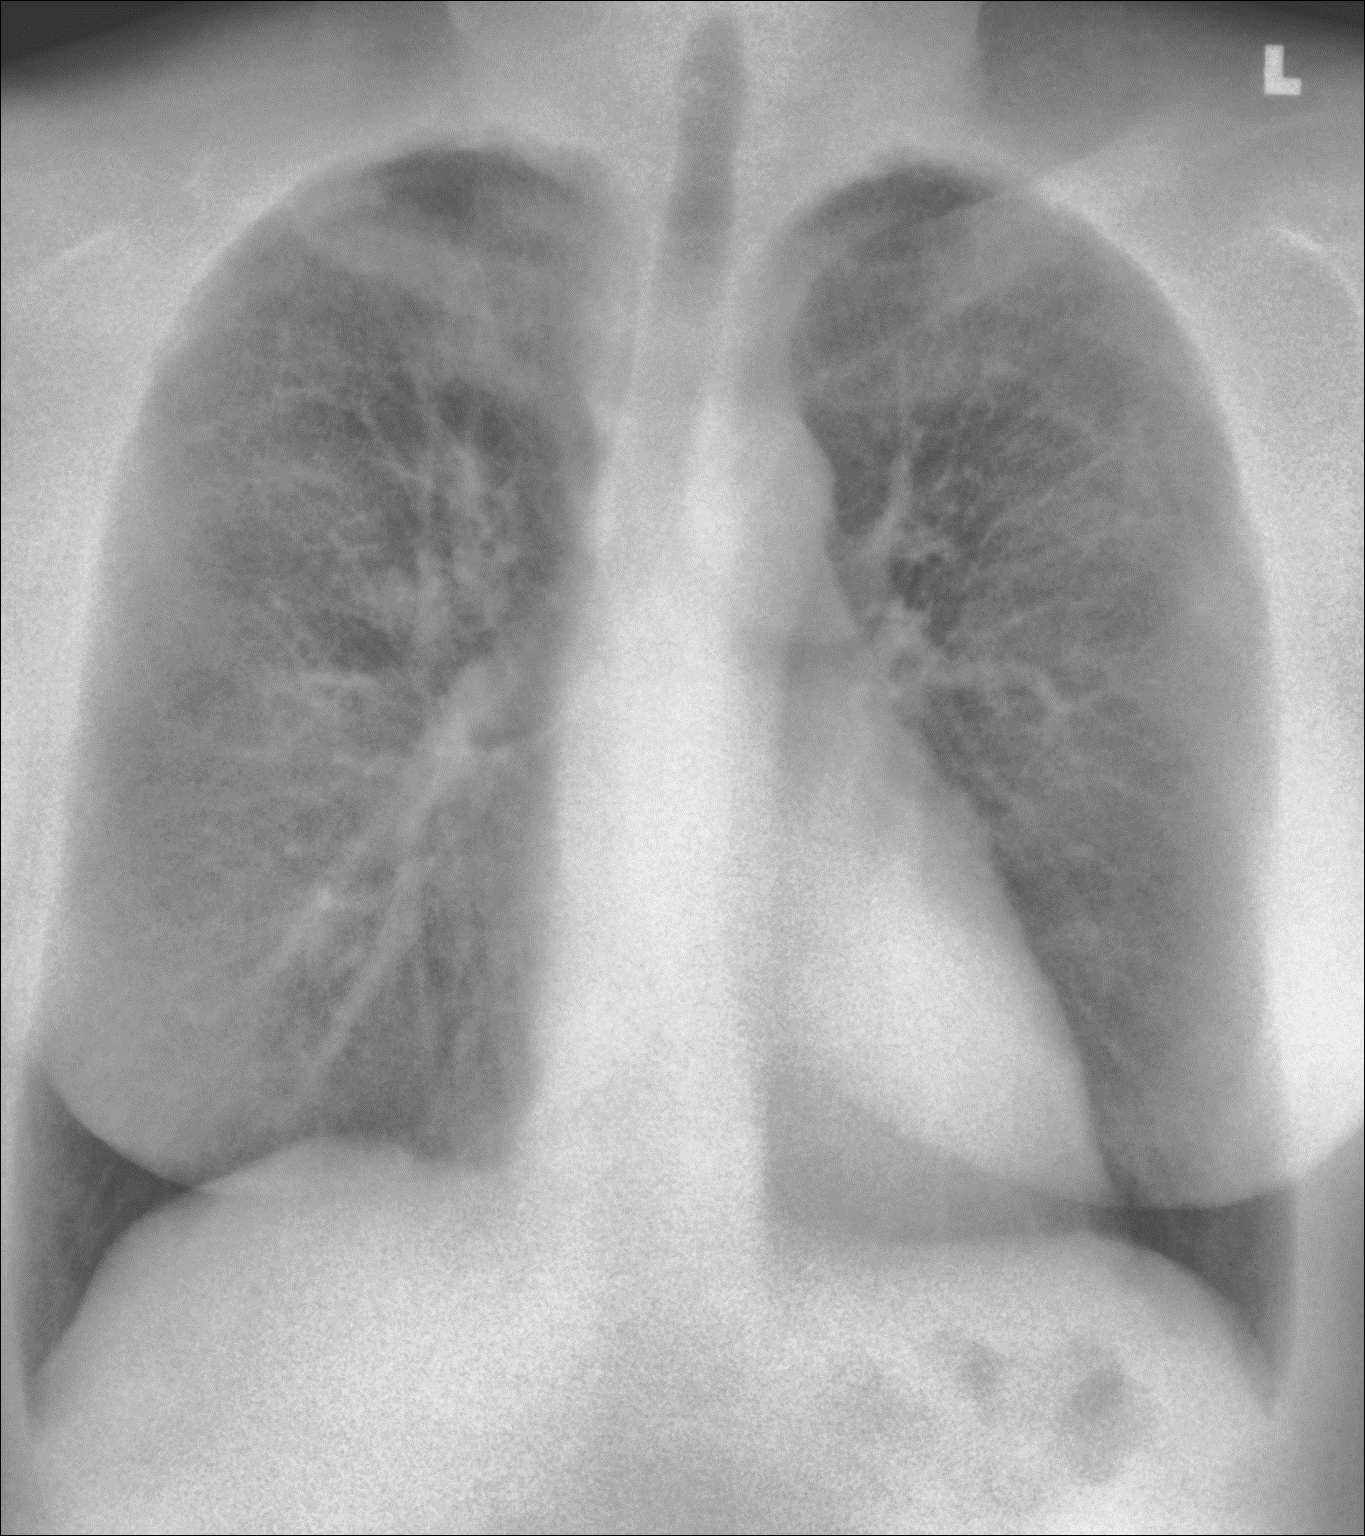

Conventional radiography compresses all anatomical information into a single image. In complex clinical environments, overlapping structures may obscure clinically relevant findings.

Spectral X-ray imaging separates bone and soft-tissue information from a single exposure, producing multiple image outputs while maintaining the same workflow as standard radiography.

Reveal™ 35C detectors use SpectralDR® technology to acquire multiple spectral images from a single X-ray exposure.

Each exposure produces:

- a conventional digital radiography image

- a bone image

- a soft-tissue image

These images allow clinicians to separate overlapping anatomical structures and visualize areas that may be less visible in conventional radiographs.

Unlike traditional dual-energy imaging techniques that require multiple exposures, SpectralDR captures these images simultaneously with a single exposure, eliminating motion artifacts and maintaining the same clinical workflow as standard portable radiography.

Soft-tissue images can reduce rib overlap and may improve visualization of pneumothorax during bedside chest X-ray examinations.

Spectral imaging can enhance visualization of lung opacities by separating bone from soft tissue, potentially improving evaluation of pneumonia and other lung conditions.